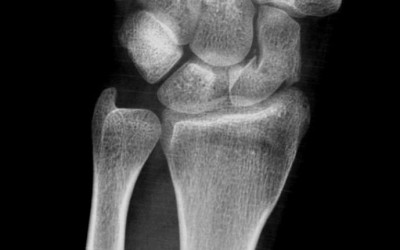

Carpal ligaments injuries

Created:21-01-2013 || Updated: 10-02-2020